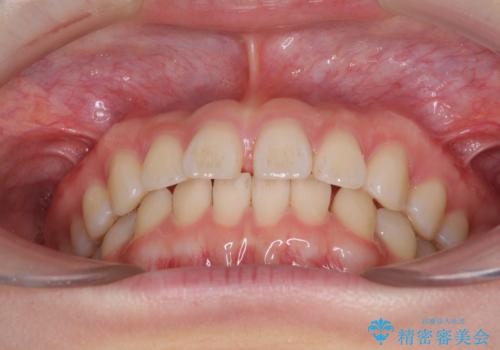

インビザラインによるすきっ歯の改善

- 上の前歯の隙間を気にして来院された患者様です。

インビザラインにより、隙間を閉じながら、隙間の原因であるディープバイトを改善していくこととしました。